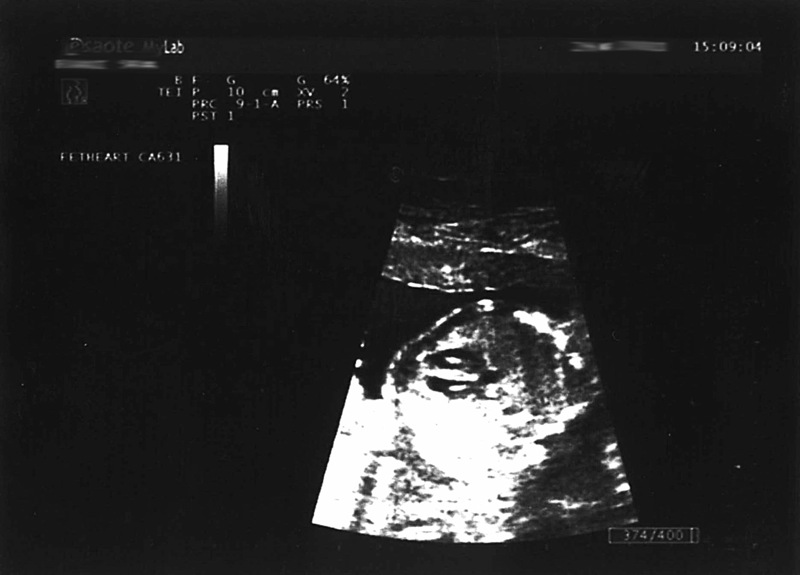

Avete sentito che velocità? Impressionante! Pensate che normalmente un cuore umano batte circa 72 volte in un minuto. Quello di un feto arriva tranquillamente a 140-160 battiti al minuto ed è udibile durante l’ecografia già alla terza settimana di gestazione. Mano a mano che i mesi passano, le pulsazioni calano, fino a 110 battiti circa al momento del parto. Pensate che il cuore è tra i primissimi organi a formarsi nell’embrione. Praticamente c’è questo esserino di pochissimi decimi di millimetro che è tutto cuore. Qui sotto vediamo il tracciato ecografico, fatto in una successiva ecografia.

E questo è un particolare del cuore: si vedono chiaramente le due cavità nere a punta, che corrispondono ai ventricoli

Ecco le cavità ancora più da vicino. Durante l’ecografia morfologica, l’esame ecografico in cui si controllano tutti gli organi del nascituro, il cuore del feto viene scandagliato nei minimi dettagli, per capire se ci siano tutte le parti che compongono quest’organo fondamentale per la vita.